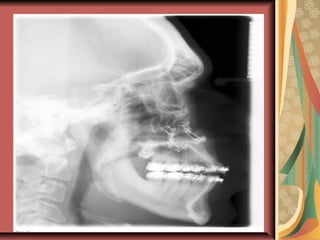

Pre op Cephelogram Post op Cephelogram

Cont… Pre opCephelogram Post op Cephelogram